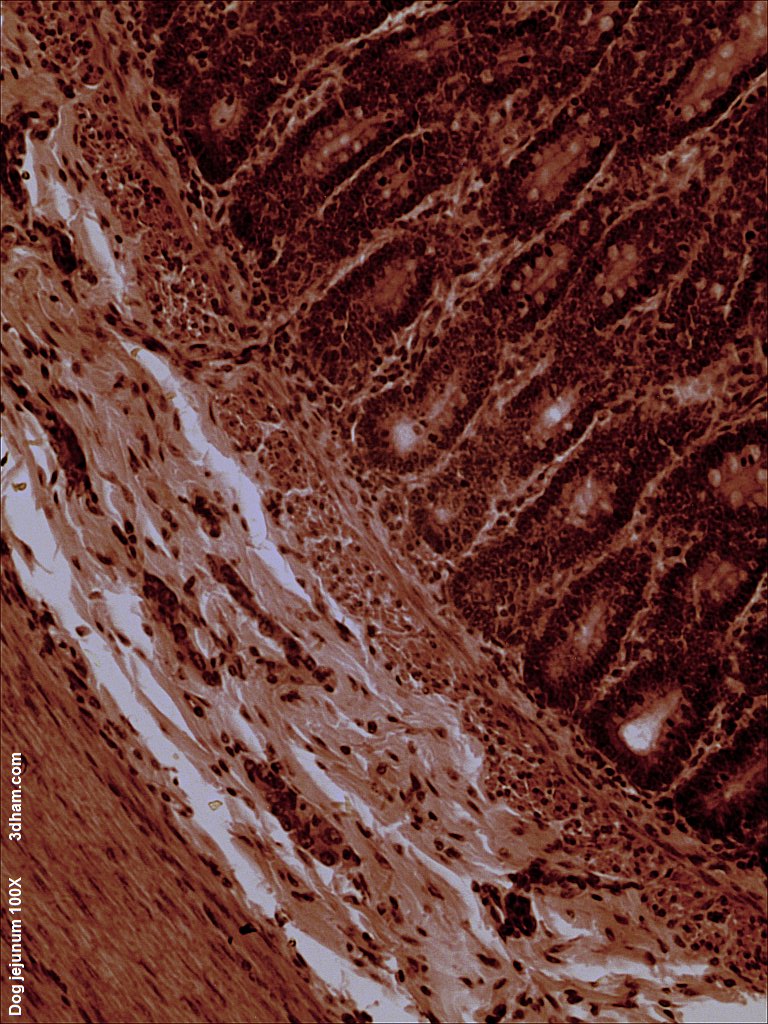

빈창자의 내부 표면은 섭취된 음식에 노출되어 있으며, 융모라고 하는 손가락 모양의 점막 돌기로 덮여 있다. 이 융모는 섭취한 음식물로부터 영양소를 흡수할 수 있는 조직의 표면적을 증가시킨다. 이 융모를 덮는 상피 세포에는 미세융모가 있다. 빈창자와 돌창자를 통한 상피 세포를 가로지르는 영양소 수송에는 설탕 과당의 수동 수송과 아미노산, 작은 펩타이드, 비타민, 대부분의 포도당의 능동 수송이 포함된다. 빈창자의 융모는 십이지장이나 돌창자의 융모보다 훨씬 길다.[1]빈창자의 pH는 일반적으로 7에서 8 사이(중성 또는 약간 알칼리성)이다.[1]

빈창자와 돌창자는 장간막에 의해 매달려 있어 복강 내에서 장의 큰 이동성을 부여한다. 또한 원형 및 종 방향의 민무늬근을 포함하여 연동 운동으로 알려진 과정을 통해 음식을 이동시키는 데 도움이 된다.[1]

빈창자는 브루너샘(십이지장에서 발견됨)이나 페이어판(돌창자에서 발견됨)이 거의 없다. 하지만, 장간막에 몇 개의 빈창자 림프절이 매달려 있다. 빈창자는 영양소 흡수를 위한 표면적을 늘리는 점막하층의 큰 원형 주름인 원형 주름이 많이 있다. 원형 주름은 빈창자에서 가장 잘 발달되어 있다.[1]

빈창자와 돌창자 사이에는 경계선이 없다. 그러나 미묘한 조직학적 차이점이 있다.[1]

- 빈창자는 돌창자보다 장간막 내에 지방이 적다.[1]

- 빈창자는 일반적으로 돌창자보다 직경이 더 크다.[1]

- 빈창자의 융모는 길고 손가락 모양의 돌출부처럼 보이며, 조직학적으로 식별 가능한 구조이다.[1]

- 전체 장관의 길이에는 림프 조직이 포함되어 있지만, 돌창자만이 다량의 페이어판을 가지고 있으며, 이는 다수의 림프구와 미세 주름 세포와 같은 면역 세포를 포함하는 비피막 림프 소절이다.[1]